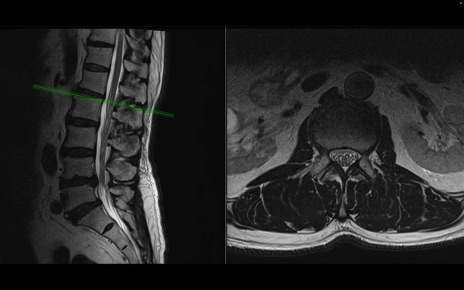

【整形】TIPS症例2 腰椎MRI 横断像と矢状断像

【症例】70歳代男性

【主訴】左下肢痛

【現病歴】2週間前くらいから腰痛、左下肢痛あり。左臀部から大腿、下腿外側のしびれが常時ある。歩行とともに同部位の痛みあり。

【身体所見】Lasegue70-/60+、Bragard-/±、PTR ±/±、ATR -/-、IP 5/5、TA 5/4、TS 5/5、EHL 右第1足趾なし/3、FHL 5/5、hypersthesia(-)、足背動脈触知良好

異常所見と診断は?